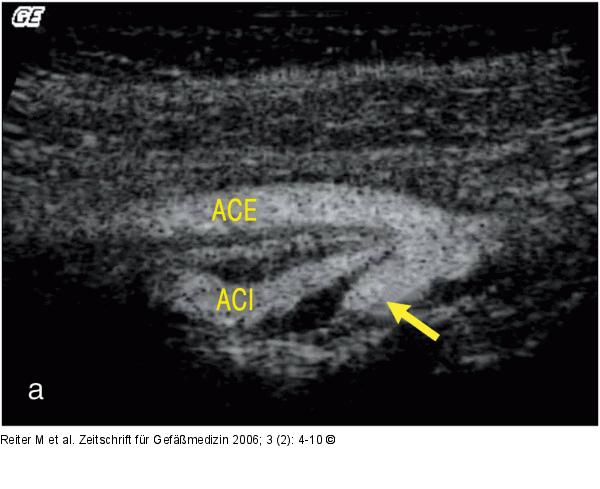

Abbildung 2a-c: B-Flow - Plaque Tief ulzerierte Plaque mittels B-Flow- (a), Farbdoppler (b) und i. a. DSA (c). (Z) zeigt das Ulkus. |

Abbildung 2a-c: B-Flow - Plaque

Tief ulzerierte Plaque mittels B-Flow- (a), Farbdoppler (b) und i. a. DSA (c). (Z) zeigt das Ulkus. |